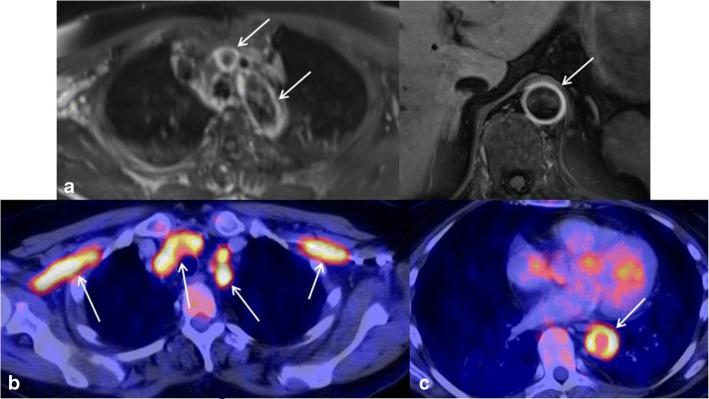

Vasculitides are characterized by mostly autoimmunologically induced inflammatory processes of vascular structures. They have various clinical and radiologic appearances. Early diagnosis and reliable monitoring are indispensable for adequate therapy to prevent potentially serious complications. Imaging, in addition to laboratory tests and physical examination, constitutes a key component in assessing disease extent and activity. This review presents current standards and some typical findings in the context of imaging in vasculitis with particular attention to large vessel vasculitides.

Recently, imaging has gained importance in the management of vasculitis, especially regarding large vessel vasculitides (LVV). Recently, EULAR (European League Against Rheumatism) has launched its recommendations concerning the diagnosis of LVVs. Imaging is recommended as the preferred complement to clinical examination. Color-coded duplex sonography is considered the first choice imaging test in suspected giant cell arteritis, and magnetic resonance imaging is considered the first choice in suspected Takayasu's arteritis. Due to diversity of clinical and radiologic presentations, diagnosis and therapy monitoring of vasculitides may constitute a challenge. As a result of ongoing technological progress, a variety of non-invasive imaging modalities now play an elemental role in the interdisciplinary management of vasculitic diseases.